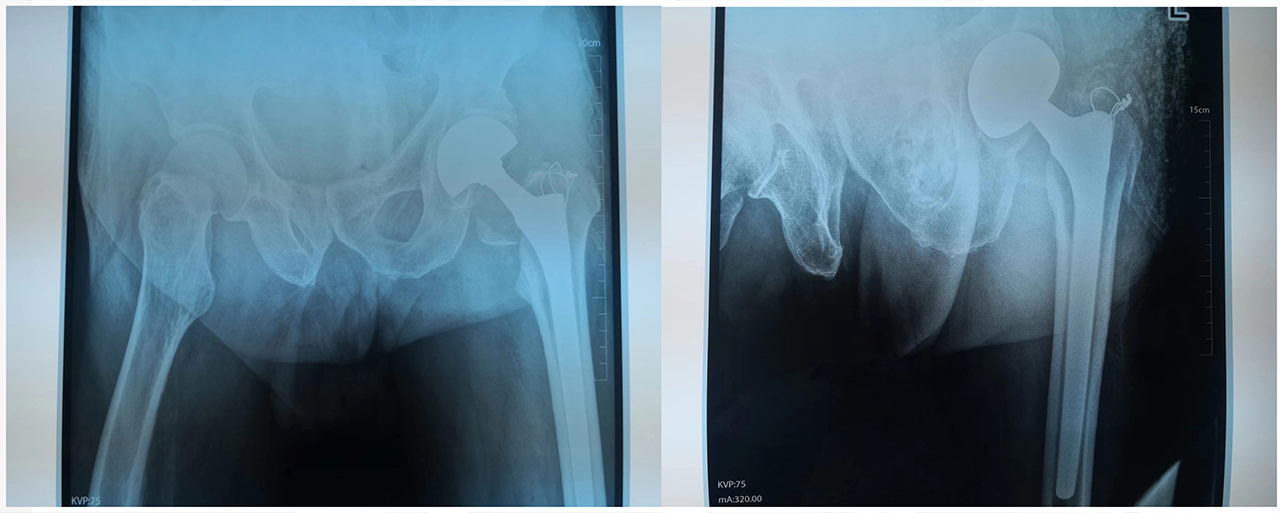

图说:患者术中DR片